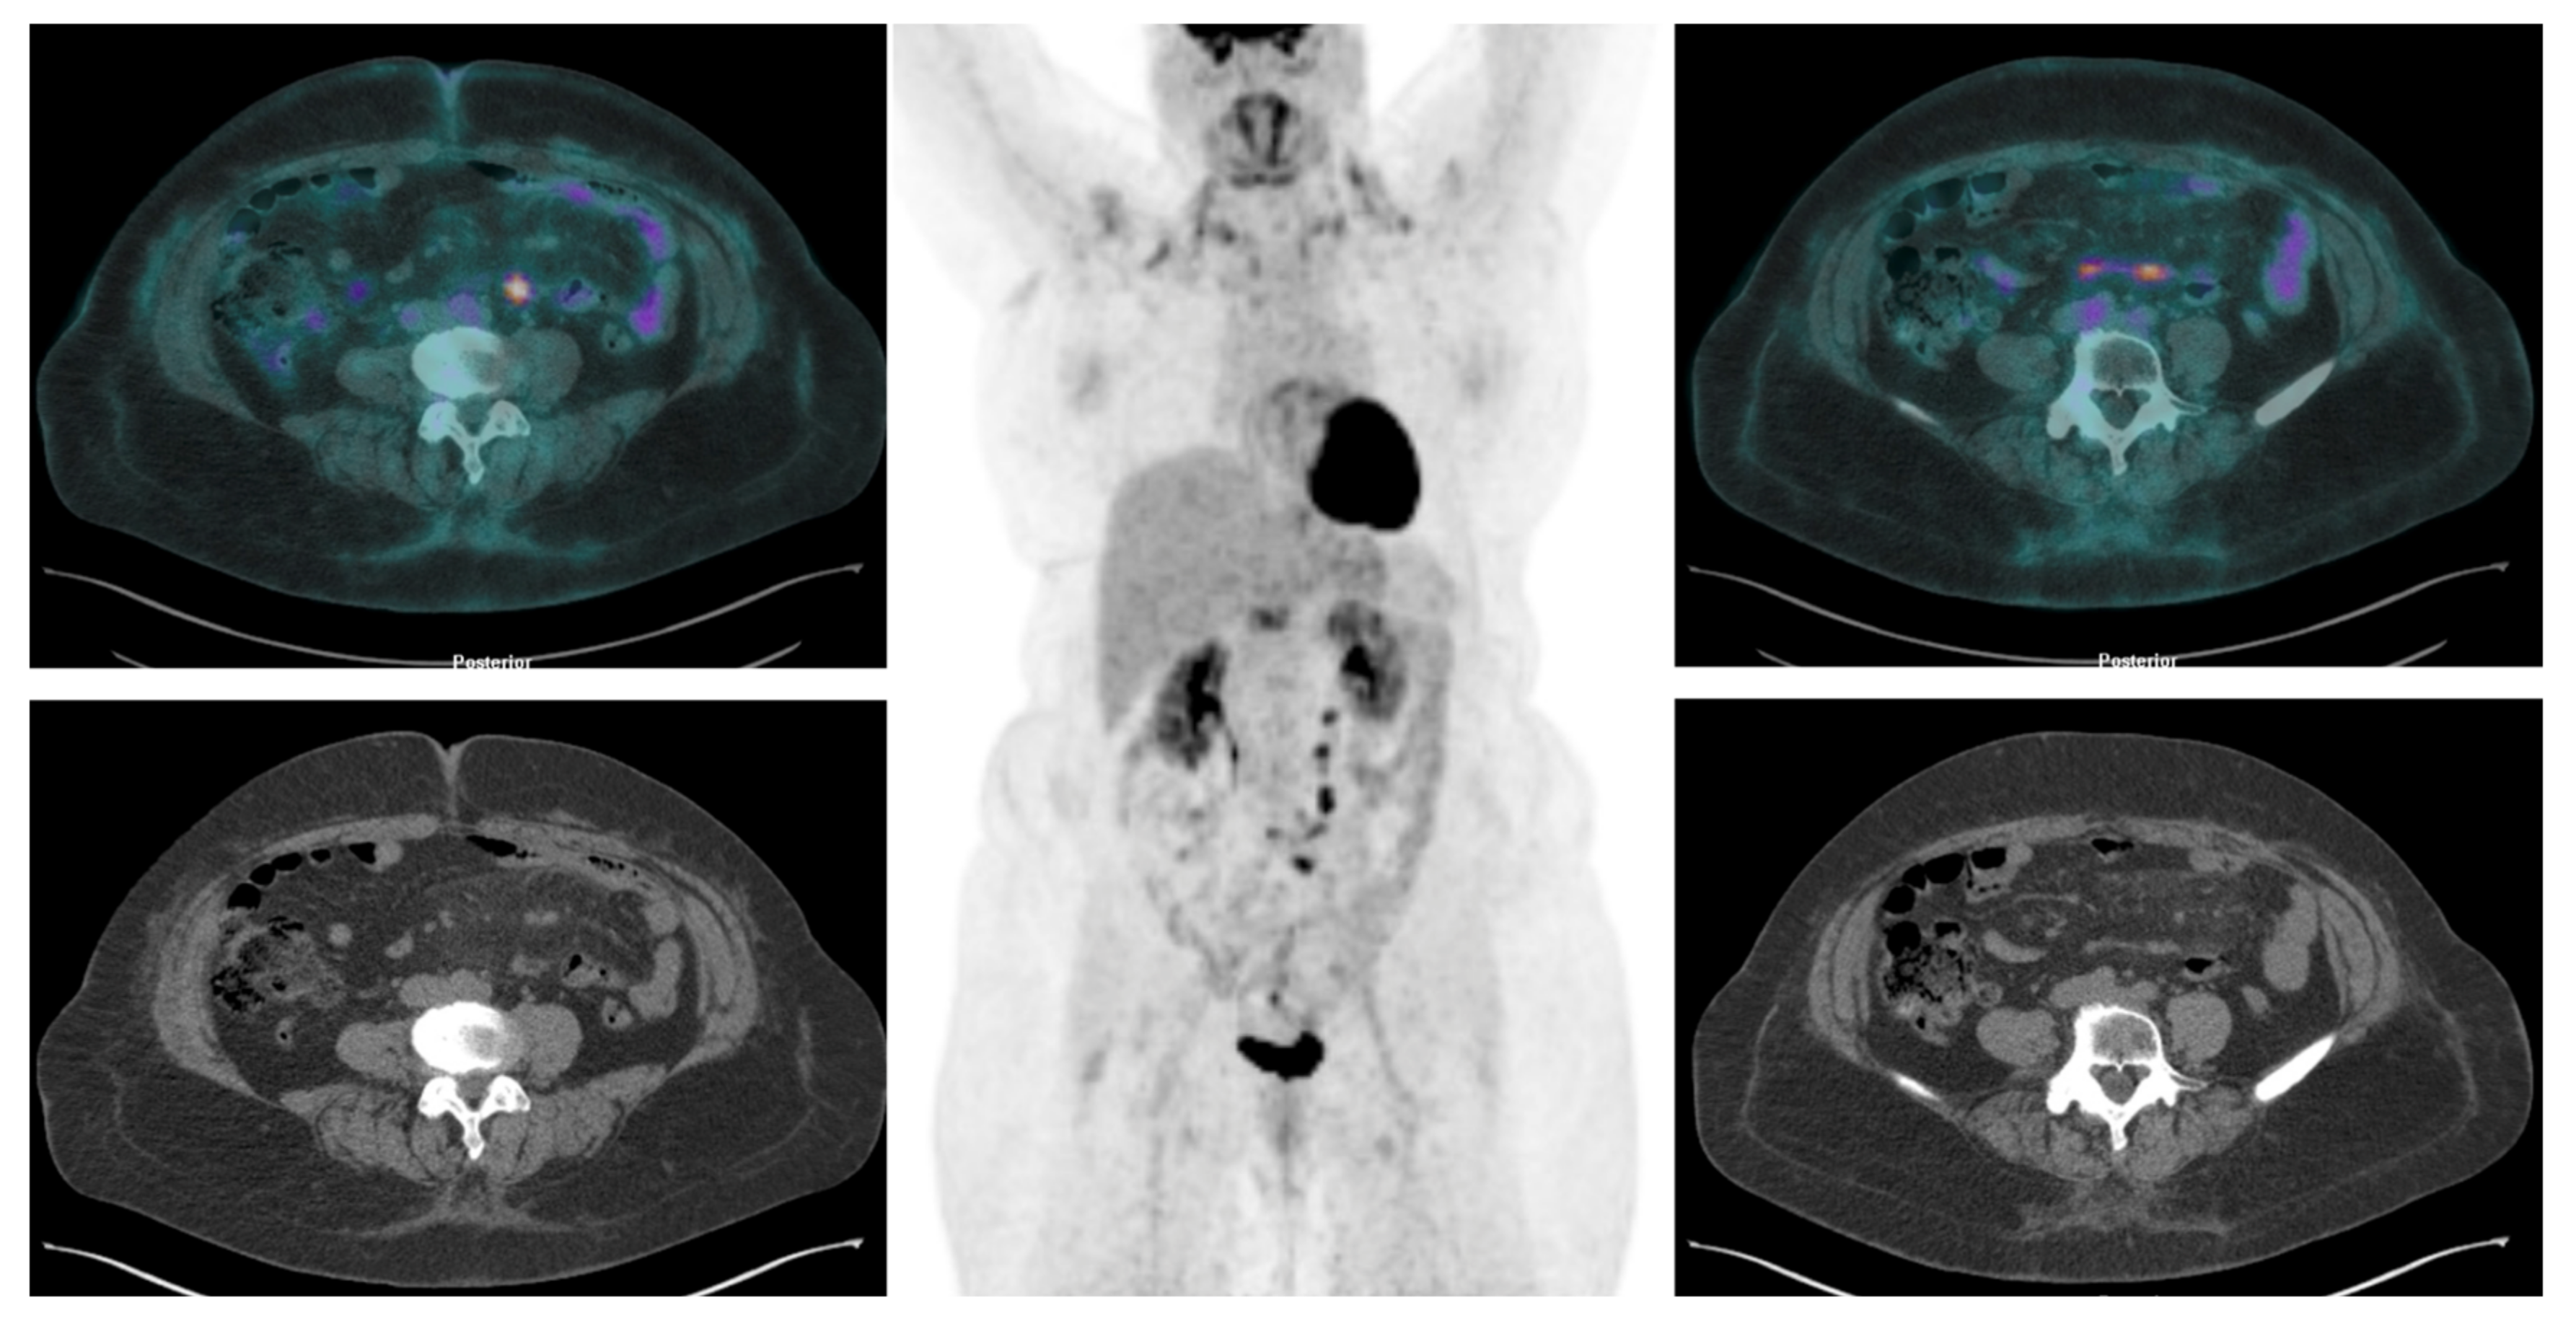

Over the past decade, numerous studies have highlighted the ability of [18F]FDG PET/CT over CT in detecting lymphadenopathies and peritoneal distant metastases associated with solid tumors (Figure 5 and Figure 6).

Figure 5. [18F]FDG PET/CT revealed a nodular hypermetabolic lesion in the mesenteric region and other foci of increased [18F]FDG accumulation in mesenterial soft tissue.